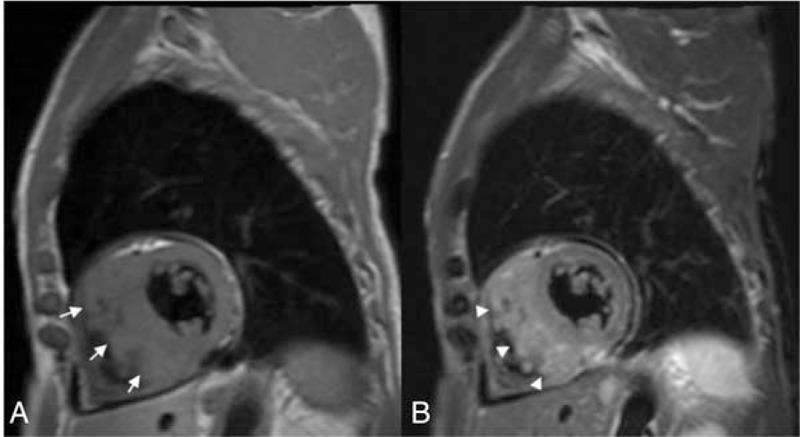

Metastatic hepatocellular carcinoma (HCC) of the right ventricle is very rare and difficult to diagnosis.A 79-year-old man who underwent right hemi-hepatectomy for HCC was admitted to our hospital for chest pain, severe dyspnea, and orthopnea. The echocardiogram showed a tumor located in the right ventricle. A biopsy was obtained, and histopathological findings confirmed metastatic HCC. Palliative resection of the tumor was performed.There is no standard treatment for metastatic HCC into the right ventricle. Thus, treatment should be individualized to the patient, and a multidisciplinary approach should be used.

右心室转移性肝细胞癌(HCC)非常罕见且诊断困难。一名因HCC接受右半肝切除术的79岁男性因胸痛、严重呼吸困难和端坐呼吸入住我院。超声心动图显示右心室内有一个肿瘤。进行了活检,组织病理学检查结果证实为转移性HCC。对肿瘤进行了姑息性切除。对于转移至右心室的HCC尚无标准治疗方法。因此,治疗应根据患者个体情况而定,并采用多学科方法。